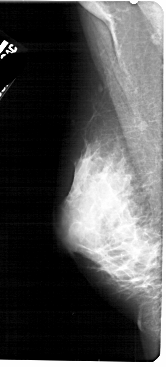

A_1746_1.RIGHT_MLO

RIGHT_MLO LINES 5431 PIXELS_PER_LINE 2416 BITS_PER_PIXEL 12 RESOLUTION 43.5 OVERLAY